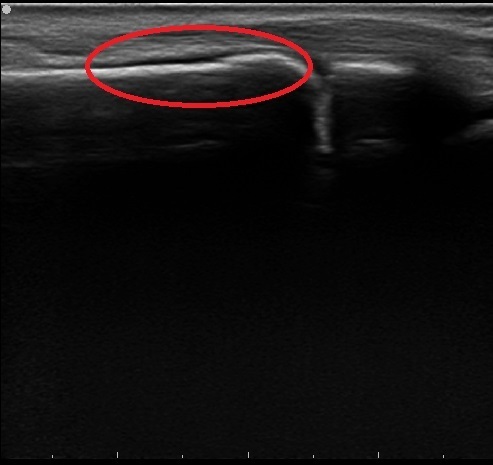

牽引前のエコー画像

牽引後のエコー画像

エコー観察にて骨折と判断。

愛護的な牽引・簡易固定を施行。翌日の朝、提携先の整形外科に紹介・受診。